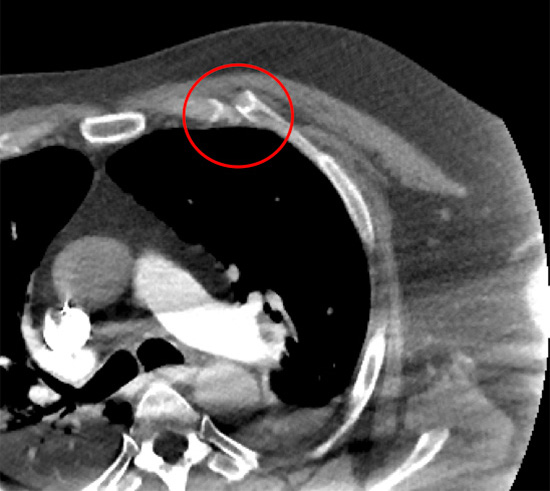

Manubriosternal junction or Sternal angle (highlighted with red circle)